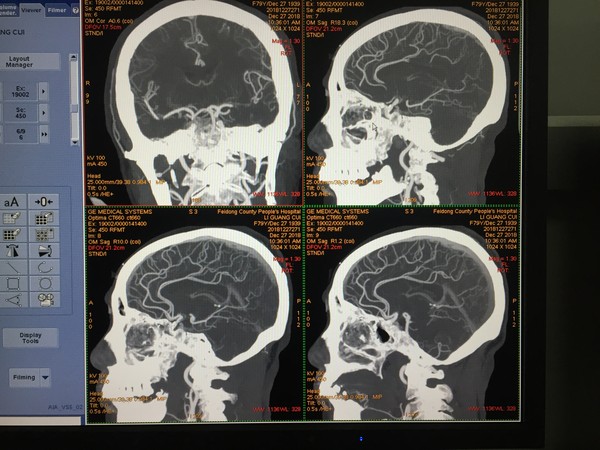

为进一步提升医疗技术水平,12月27日我院影像科CT室在姚怀刚主任的带领下成功开展了CTA检查,当天我科顺利完成了两例冠脉CTA及四例头颈部CTA检查,及时为临床科室相关疾病的诊疗提供了确定性的意见和建议。

CT血管造影(CTA)是将CT增强技术与薄层、大范围、快速扫描技术相结合,通过合理的影像后处理,清晰显示全身各部位血管细节,具有无创和操作简便的特点,有助于医师术前直观、准确、多角度评价患者病变的部位、范围、管腔狭窄程度等。对于血管变异、血管疾病以及显示病变和血管关系有重要价值。目前,我院CT室已成功开展头颈部、冠状动脉、肺动脉、 肠系膜动脉、胸腹主动脉、肾动脉、腹主双下肢等部位的CTA,给临床带来了很大帮助。